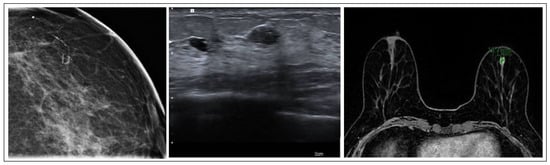

ADH is one of the most frequently recognized B3 lesions in breast pathology. It often correlates with grouped microcalcifications, nodules, or atypical densities visible on mammograms. Predominantly, ADH is detected in cases where calcifications appear on mammograms, constituting a significant majority (81.6%), while, in other studies, the prevalence of ADH detected alongside microcalcifications is even higher (86%) [7]. The MRI in these cases shows a lesion with nonspecific characteristics, such as a focal non-mass area or a small, irregular mass (Figure 1). Histologically, ADH is a small, low-grade, clonal intraductal lesion, that generally measures up to 2 mm in maximum diameter or consists of segments of a terminal ductal lobular unit.

Figure 1. ADH radiological features.